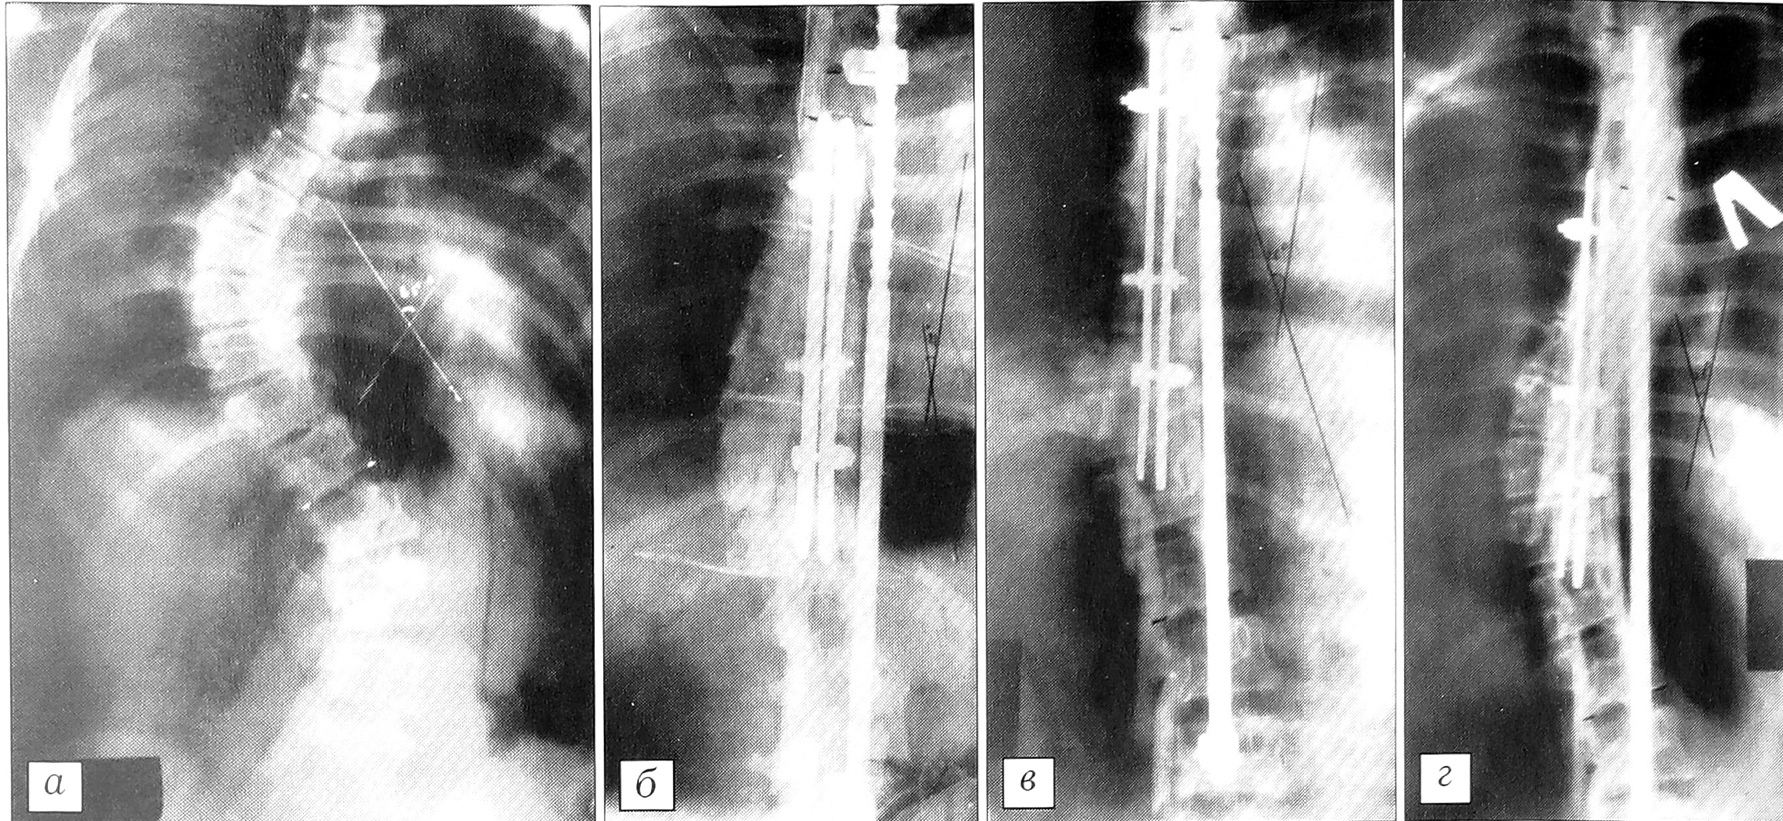

У 23 больных основной группы (подгруппа 1а) с углом искривления более 55° и относительно лабильной формой искривления коррекция и стабилизация позвоночника осуществлена пластинчатыми эндокорректорами. Эндокорректоры разработаны нами (пат. Р 990038 Азербайджанской Республики от 1999 г.) в нескольких вариантах и могут использоваться и при сложных многоплоскостных деформациях позвоночника. Один из вариантов эндокорректора изготовлен из упругого титанового сплава, что позволяет оказывать на позвоночник динамическое поперечно-корригирующее воздействие (рис. 2). Операции с применением предложенных эндокорректоров технически несложны и не требуют немедленной послеоперационной корсетной иммобилизации. Это существенно упрощает послеоперационное ведение больного. Корригирующий эффект эндокорректора складывается из поперечно и продольно направленных векторов сил и его деротирующего действия. Наш клинический опыт и проведенные гистоморфологические исследования показывают, что распространенное мнение о слабости ткани остистых отростков позвонков и их непригодности в качестве опоры для корригирующих имплантатов не имеет под собой достаточных оснований и должно быть пересмотрено.

При более ригидных сколиозах мы, учитывая мнение С.Т. Ветрила и соавт. [4] о преимуществах сочетания корригирующих устройств, у 5 больных (подгруппа 16) применили комбинацию из дистрактора Харрингтона и пластинчатого эндокорректора собственной конструкции (рис. 3). После установки дистрактора Харрингтона с вогнутой стороны и предварительной коррекции укладывали пластинки эндокорректора на основания остистых отростков с обеих сторон с максимальным охватом позвонков основной дуги искривления. Через основания остистых отростков и отверстия пластин проводили титановые болты и затягивали их гайками. При этом визуально определялось существенное ослабление напряжения на стержне и крючках дистрактора Харрингтона, что создавало возможность для дополнительной коррекции. Операцию заканчивали междужковым и частично межпоперечным спондилодезом костными аутоили аллотрансплантатами. У 2 больных для мобилизации крайне ригидной деформации перед установкой эндокорректоров была произведена лигаментокапсулотрансверзотомия на вогнутой стороне основной дуги.

При применении данной методики достигнута коррекция в среднем 28,1° (21-35°) при исходной величине угла искривления от 55 до 68°. Наименьшая коррекция получена у 5 больных с более ригидными формами сколиоза (21-25°). У 18 больных с мобильностью позвоночника свыше 12° коррекция составила от 25 до 35°.

Ретроспективный анализ показывает, что операции с применением пластинчатых эндокорректоров наиболее эффективны при грудном, грудопоясничном и поясничном сколиозе, когда угол искривления не превышает 65° при индексе стабильности по Казьмину менее 0,8. При рентгеноторсиометрическом исследовании выявлено, что пластинчатые эндокорректоры дают и заметный деротирующий эффект, который более выражен на основной дуге и составляет до 10° по Perdriolle. При поясничном сколиозе деротирующий эффект конструкции может достигать 15°.

Динамика потери коррекции прослежена в сроки от 1 года до 4 лет у 17 больных. Темпы ее оказались заметно ниже, чем при использовании методики Харрингтона, потеря коррекции не превышала 40% от достигнутой во время операции.

У больных с более ригидными формами сколиоза (подгруппа 16) — мобильностью позвоночника менее 10° (индекс стабильности более 0,8), которым коррекция искривления производилась дистрактором Харрингтона в сочетании с пластинчатым эндокорректором нашей конструкции, достигнута коррекция от 32 до 46°. Анализ послеоперационных рентгенограмм показал, что применение комбинации из двух не связанных в единую систему эндокорректоров приводит к значительному уменьшению потери коррекции, которая по истечении 1,5~2 лет после операции не превышала 10-15°.